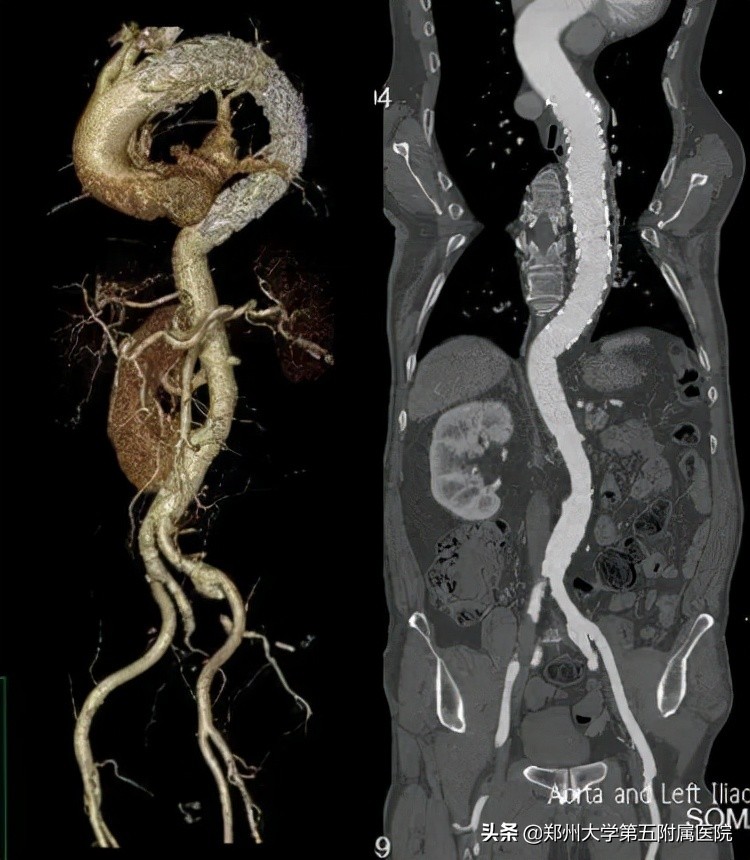

▲ 术后复查CTA,主动脉支架位置良好,各血管通畅良好